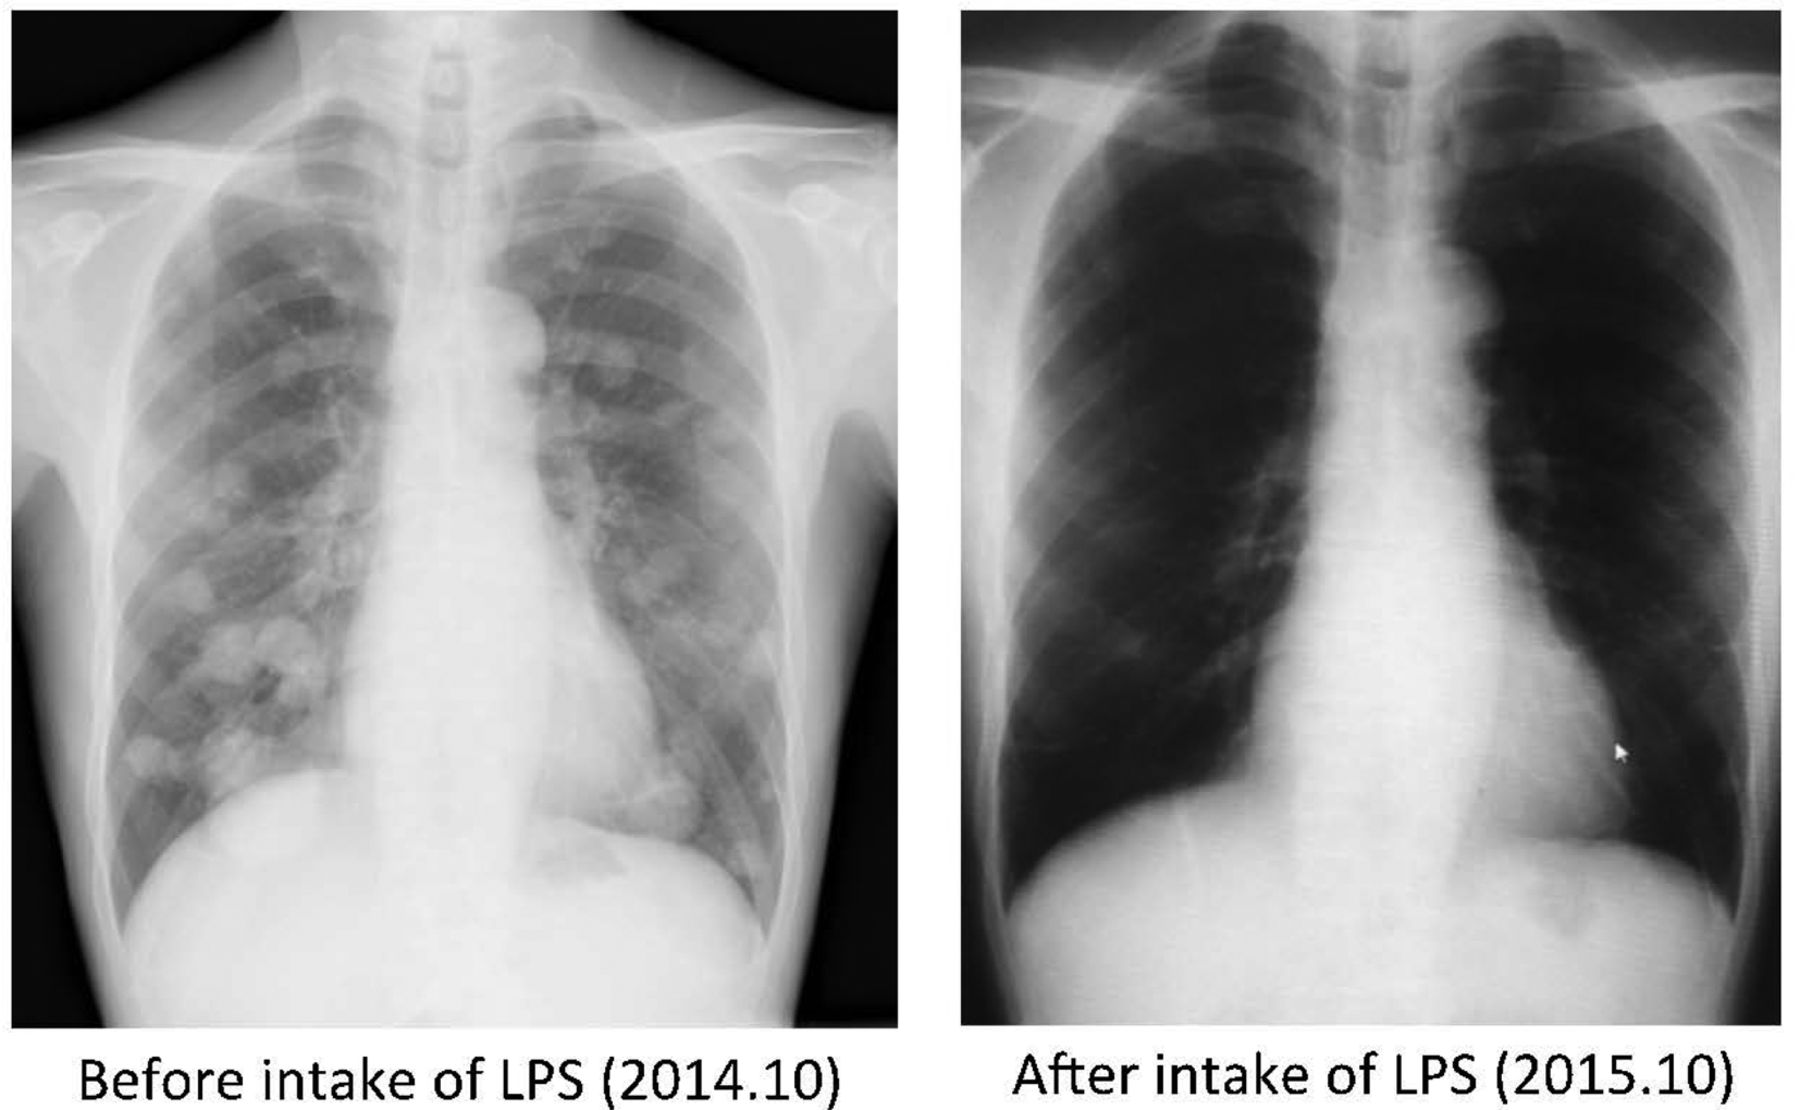

3.口服LPS前后肺部X线片对比。

图为多发转移性肺肿瘤完全消退(男性,66岁,口服LPS 1.25mg/天,持续10个月)。